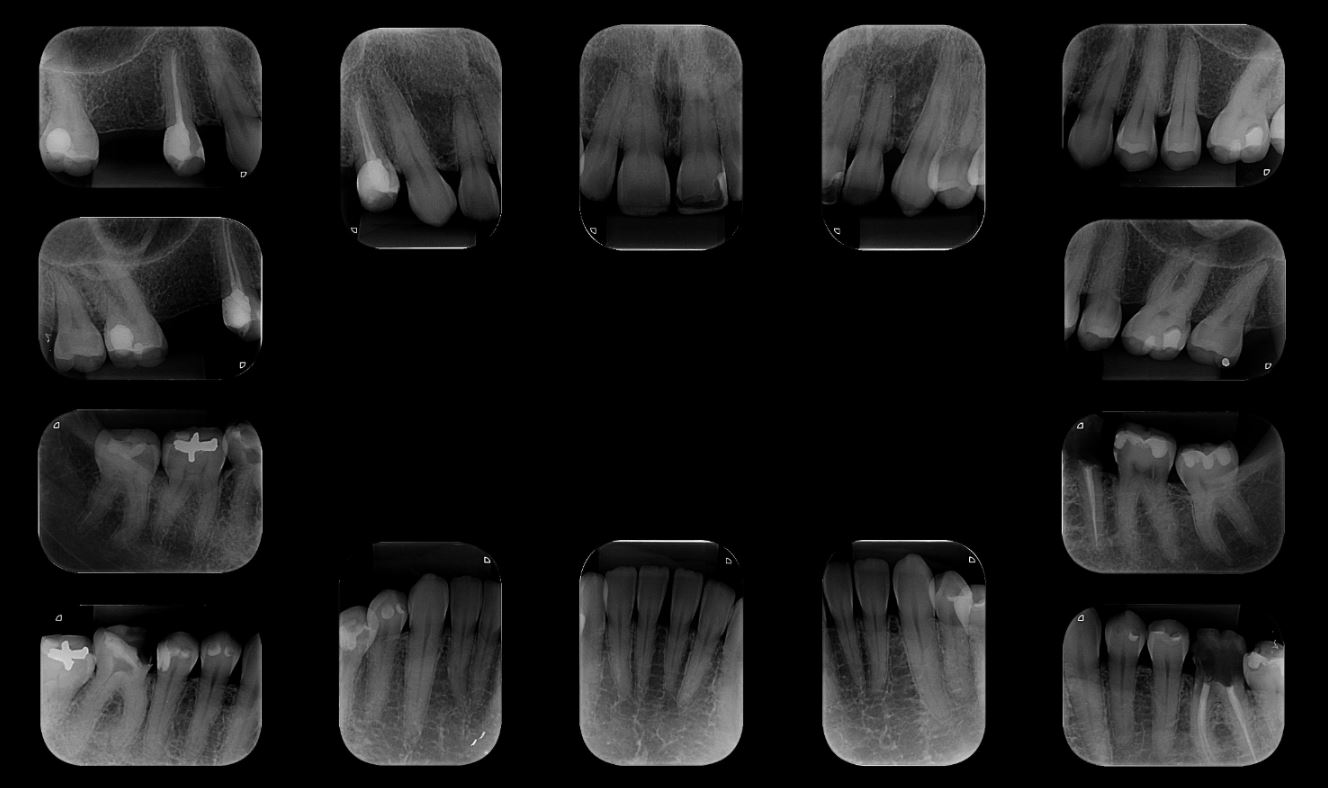

Radiografias Intraorais Digitais

Periapicais, Interproximais, Oclusais.

Realizadas com placas óticas digitais de altíssima resolução auxiliando no diagnóstico do profissional e tratamento do paciente.